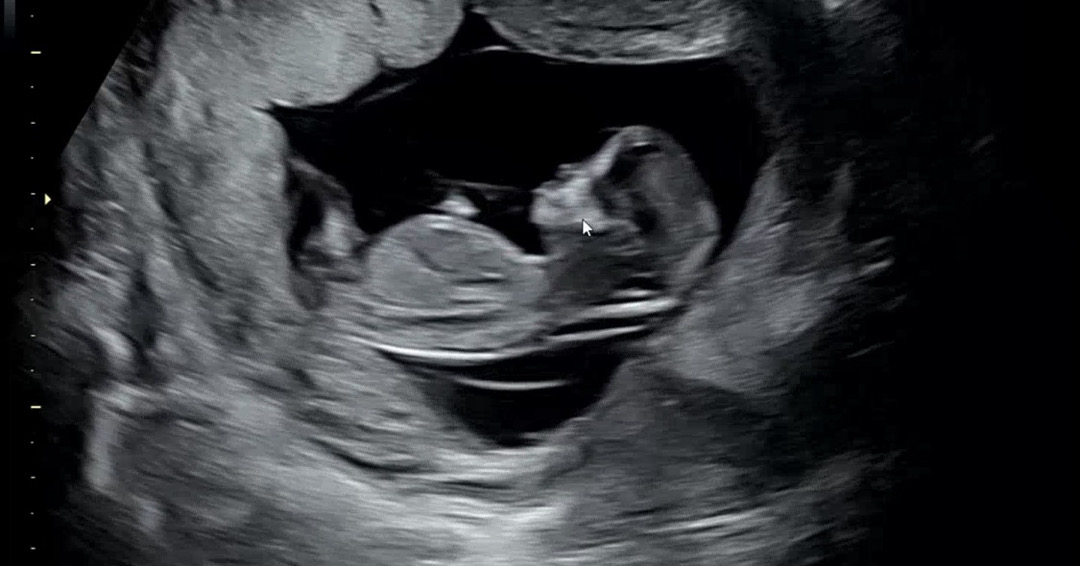

12주 각도법 궁금합니다!

각도법 가능한 사진일까요~? 성별이 궁금합니다ㅠㅠㅠ 도와쥬세요!!